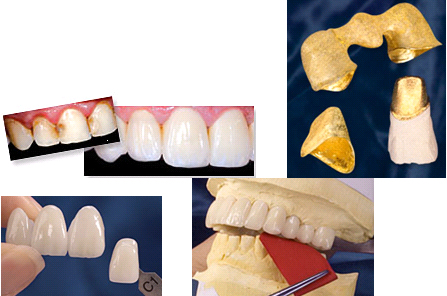

New generations of restorative dental materials help us to offer our patients beautiful and esthetic restorations. Even if you have broken teeth, old restorations with different shades or colors, or one or more teeth are missing. The use of composites or porcelain over decayed teeth and restorations can make a tremendous change in your smile. Each individual case must be evaluated first by our team of specialists in order to deliver the best treatment options.

A crown is a type of restoration that will be cemented over a prepared tooth looking to restore the form and function of the original. Decayed, broken and/or pigmented teeth compromise the normal function and esthetics for the patient. A bridge is a restoration that will replace a missing tooth making use of the two teeth adjacent to the missing tooth which will support the missing tooth. Both crowns and bridges can be made from multiple types of materials, from less to more esthetic. Each patient must be first evaluated to determine the best treatment option.